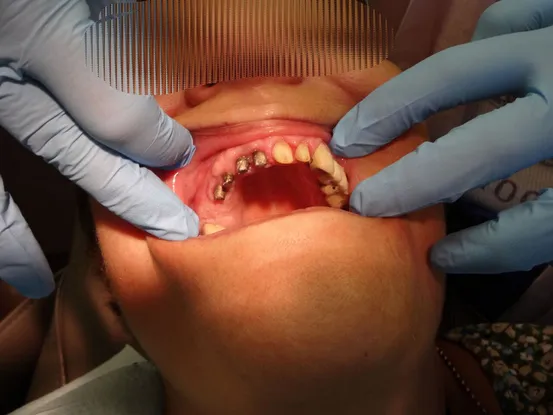

Case 4

58 year old female with unstable partial upper denture due to lack of anchor teeth on upper right quadrant. 4 implants placed and elimination of denture and improved masticatory function.